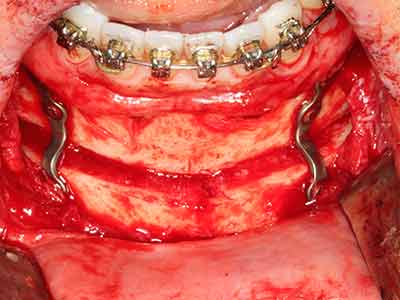

Костната тъкан е не само минерализирана структура, тя съдържа и съществено количество колагенови влакна. Това означава, че тя има не само добра компресивна сила, но и известна степен на гъвкавост, която може да се възприеме като предимство при извършване на костна аугментация. В класическата процедура по разширяване чрез костно разделяне, атрофиралият алвеоларен гребен е разделен надлъжно и внимателно разширен след достигане на подходящата остеотомна дълбочина (Фиг. 13-16), в идеалния случай без допълнително отстраняване на периостеума (Brugnami, Caiazzo et al. 2014, Stricker, Fleiner et al. 2014). Системите с винт и пластини с увеличаване на разстоянието при разширяване са доказали ефективността си при разделяне на двете костни ламели, оставайки под прага на фрактурите. В общи линии, оставащата ширина на костта от поне 3–4 mm е задължителна (Chiapasco, Zaniboni et al. 2006), за да се гарантира добра гъвкавост и достатъчно костно покритие за бъдещото поставяне на импланти. Ако е необходимо, вертикалната остеотомия на едната или двете страни може да подобри гъвкавостта. Комбинацията с допълнителни техники за аугментация, особено в букалната страна, е описана като алтернатива на класическата техника.

Процедурата по разделяне е атравматична и няма голяма загуба на пространство, използвайки пиезотриони, и няма значителна разлика между импланти в разделени челюсти и импланти в алвеоларния гребен без костен дефицит (Chiapasco, Zaniboni et al. 2006, Danza, Guidi et al. 2009). Въпреки това, важно е да има достатъчно и продължително охлаждане, особено при ограничено и дълбоко разделяне, за да се избегне термичен стрес в апикално-остеотомните зони.

Фиг. 13: Подходяща иригация с остатъчна 4 mm дебелина на костта е важна за този 52-годишен пациент по време на разделянето на костта.